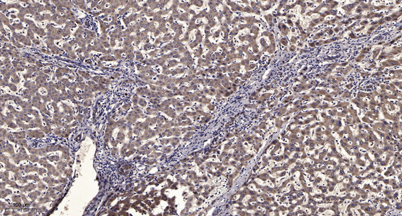

Product name: SMYD2 rabbit pAb

Dilutions: WB 1:500-2000;IHC-p 1:50-300; ELISA 2000-20000